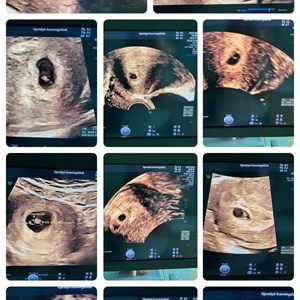

12 uger - nakkefoldsscanningen. Jeres 1. officielle scanning på hjemsygehuset - Kan laves...

12 uger - nakkefoldsscanningen. Jeres 1. officielle scanning på hjemsygehuset - her er hv...

De små stjernestunder 🫶 Bare 12 uger og gør sin stjerne-entré overfor mor og far 🤩 #nak...